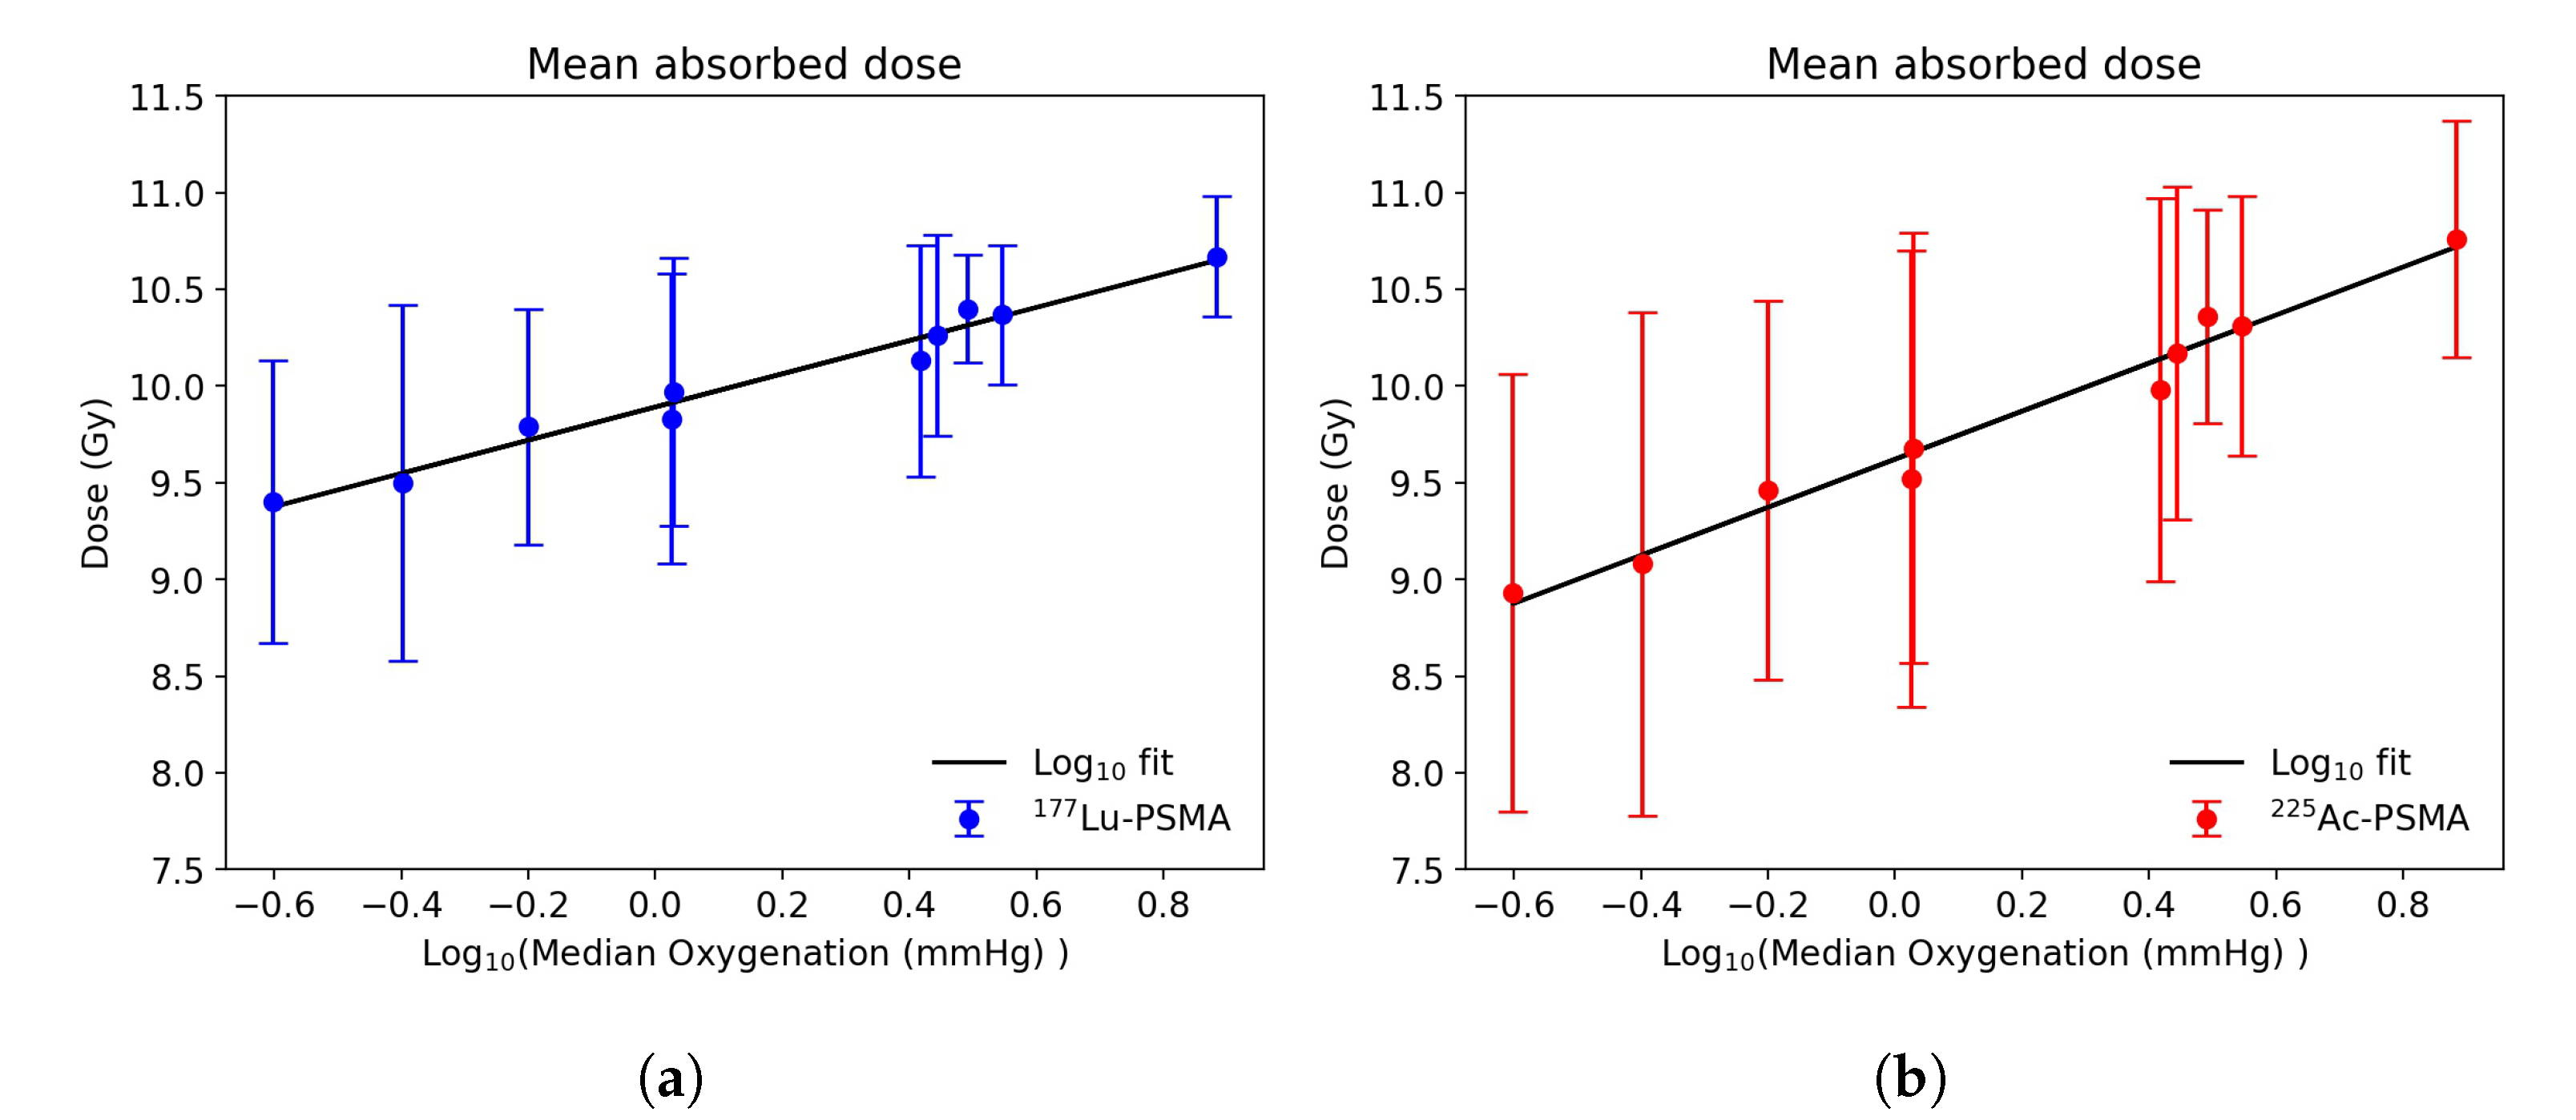

3.2. Dose Distribution in Tumor Microenvironment

3.3. Radiobiological Efficacy Analysis